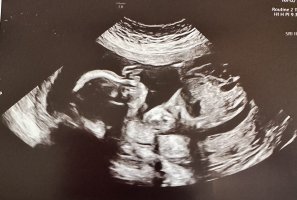

Tipper gutt. Har du funnet det ut?Ikke her heller sikkert? Mente kanskje det under beina kanskje kunne være kjønnsorganet, men er sikker noe annet ja..

Nei, enda litt over to uker tilTipper gutt. Har du funnet det ut?

tipper du gutt eller er det noe i bildene som får deg til å tippe det?Nei, har egentlig ikke så altfor mye å gå etter. Noe med ansiktet, spisse/skarpe ansiktsdetaljer. Om en ser på hodefasongen ser det ut som jente (rundt) på ene bildet men så ser det ut som gutt (mere firkantet) på det andre bildet. Så det er vanskelig å si!Nei, enda litt over to uker tiltipper du gutt eller er det noe i bildene som får deg til å tippe det?

Jeg er også ekstremt spent på oul. 15 dager igjen nå!Synd at jeg ikke så denne tråden før toul. Ser ingen nub på bildet vi fikk. Nå er jeg veldig spent på oul.

Så stas! Gratulerer med en liten jenteDet kommer en liten jente til oss, så du hadde rett her! Det blir skikkelig stas etter 3 gutter!

Her kommer det gutt nr 2

Det ble jente! vi er veldig glade og nub-theory utført av chat gpt stemte altså.Er jente jaHolder en knapp på jente jeg![]()